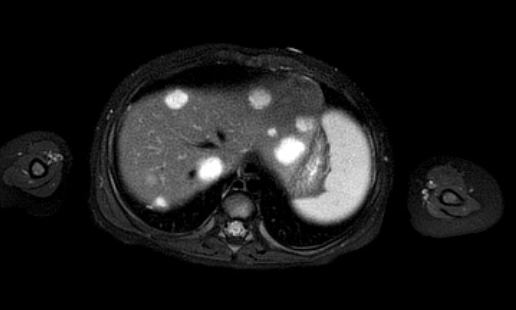

Ví dụ 1

Một bé gái ba tuổi có khối u thận trái và huyết khối khối u lớn trong tĩnh mạch thận và tĩnh mạch chủ dưới. Có di căn gan (phát hiện không thường gặp) và di căn phổi.

Lưu ý huyết khối u trong tĩnh mạch thận trái kéo dài vào tĩnh mạch chủ dưới.